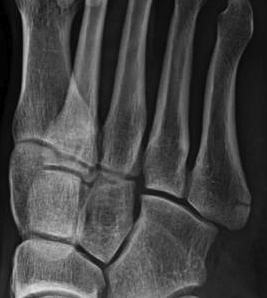

Xray

Progression to nonunion of zone 2 fracture with nonoperative care

Torg Classification

| Type I | Type II | Type III |

|---|---|---|

| Acute | Delayed union | Nonunion |

|

Narrow fracture line No sclerosis No cortical reaction No periosteal hypertrophy |

Increased fracture line Both cortices Some sclerosis Some periosteal hypertrophy |

Significant sclerosis Significant cortical hypertrophy |